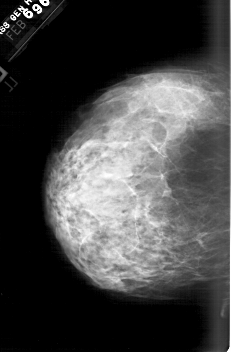

ics_version 1.0 filename A-1564-1 DATE_OF_STUDY 6 2 1996 PATIENT_AGE 43 FILM FILM_TYPE REGULAR DENSITY 4 DATE_DIGITIZED 14 9 1998 DIGITIZER HOWTEK 43.5 SEQUENCE LEFT_CC LINES 6331 PIXELS_PER_LINE 4156 BITS_PER_PIXEL 12 RESOLUTION 43.5 NON_OVERLAY LEFT_MLO LINES 5941 PIXELS_PER_LINE 4321 BITS_PER_PIXEL 12 RESOLUTION 43.5 NON_OVERLAY RIGHT_CC LINES 6226 PIXELS_PER_LINE 4261 BITS_PER_PIXEL 12 RESOLUTION 43.5 OVERLAY RIGHT_MLO LINES 6271 PIXELS_PER_LINE 4501 BITS_PER_PIXEL 12 RESOLUTION 43.5 OVERLAY |